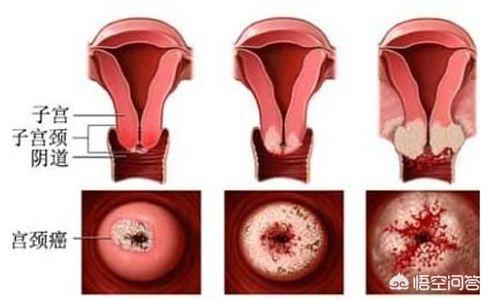

3.子宮頸部びらん

また、子宮頸部上皮細胞が異型過形成(子宮頸部上皮内新形成とも呼ばれる)を起こしていることが判明した場合は、細胞変異の程度を注意深く観察する必要がある。子宮頸部の炎症は、多くの場合、子宮頸がんにつながる可能性のある遺伝的変化を子宮頸部上皮に引き起こす危険性の高いHPV感染の結果である。

子宮頸部上皮内新生物→子宮頸がん

子宮頸部上皮細胞は、HPVに持続感染すると、異型過形成から癌化する可能性があり、その期間は最長で10年以上にも及ぶ。

中でも子宮頸部上皮内新形成は、一般に子宮頸部前癌病変とも呼ばれ、3つのグレードに分けられ、グレードが高いほど癌化しやすく、グレードが低いほど治療に適している。

一人だ、性的に活発な女性は、年に一度はTCTとHPV検査を受けるべきです。異常があれば、コルポスコピーまたは生検が必要です。

二、慢性子宮頸管炎と子宮頸部前癌病変を積極的に治療すること。性生活は衛生的でなければならない。

三、子宮頸がんワクチン接種は、子宮頸がんの発症を予防するために、条件が許せば受けることができる。

4.子宮頸部円柱上皮外反症:以前は子宮頸部びらんとも呼ばれていた。子宮頸部円柱上皮外反症は、性交渉、人工妊娠中絶、出産、感染症、外科手術などによって引き起こされ、扁平上皮の代わりに外傷を覆うように子宮頸部円柱上皮過形成を引き起こし、慢性子宮頸管炎の局所の特徴の一つであり、子宮頸癌を誘発する可能性があります。また、子宮頸癌の発生にはヒトパピローマウイルス(HPV)感染が関係しており、ハイリスクHPV感染者の中には、子宮頸部の扁平上皮-柱状上皮接合部に持続感染している場合、前癌病変や子宮頸癌が発生しやすい人がいる。

- 子宮頸部内新形成(CIN)は子宮頸癌の前癌病変であり、ヒトパピローマウイルス感染と関連している。HPVとして知られるヒトパピローマウイルスには全部で120種類以上の型があり、そのうち10種類以上が子宮頸がんの発症に深く関係している。HPV感染は子宮頸癌の99%に認められ、そのうち約70%はHPV16型とHP V18型に関連している。子宮頸部内膜症(CIN)はグレードI、II、IIIに分類され、グレードIIIではすでにin situ子宮頸がんと同等である。HPV感染に対する特異的な薬剤はない。定期的なHPV+細胞診は子宮頸がんの早期発見につながる。 HPV感染はワクチン接種で予防できる。クリニックでは、子宮頸がんの80%以上を予防できる国産品と輸入品の両方を用意している。